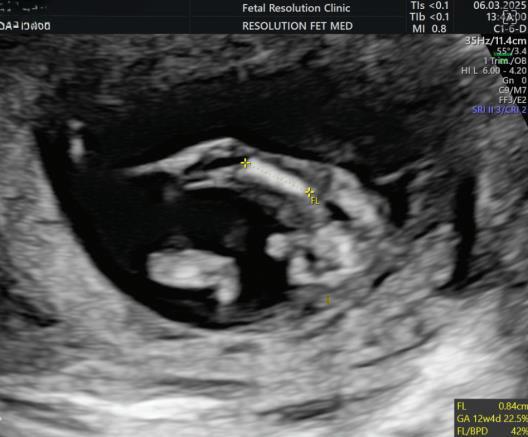

The first trimester— spanning from conception to 13+6 weeks—is no longer considered a “blind phase” of pregnancy. With the evolution of highresolution ultrasound, color Doppler and advanced biochemical screening, this period has transformed into a window of opportunity for early fetal evaluation, risk prediction and preventive strategies.

First-trimester fetal evaluation is not limited to dating the pregnancy or confirming viability—it is the foundation of predictive, preventive, and personalized obstetric care.

2. NUCHAL TRANSLUCENCY (NT) SCAN

• Done @11–13+6 weeks.

• CRL 45–84 mm.

• This is the cornerstone of first trimester screening.

MEASUREMENTS THAT CAN BE OBTAINED ON

First Trimester Fetal Evaluation:

FETAL ULTRASOUND EXAMINATION AT 11 TO 14 + 0 WEEKS: BASIC BIOMETRY INCLUDES:

Nuchal Translucency

Biperital Diameter

(a) Crown Rump Length(CRL)

(b) Biperital diameter(BPD)

(c) Nuchal Translucency(NT)

DETAILED BIOMETRY INCLUDES:

Along with basic biometry

(a) Abdominal circumference

(b) Head circumference

(c) Femur length

Abdominal Circumference

1. NT is the sonographic appearance of subcutaneous accumulation of fluid behind the fetal neck, below the skin in the first trimester of pregnancy.

2. Measured in mid-saggital section only.

3. Measured between 11-14 weeks.

4. CRL between 45-84mm.

5. Magnified to include only head and upper thorax.

6. Fetus should be in neutral position.

7. Demostrate fetus separate from amnion.

8. Measurement should be ON to ON (cross bar of the callipers should be such that it’s hardly visible and merges with white line, not nuchal fluid).

During the scan more than one measurement should be taken and maximum value should be considered.